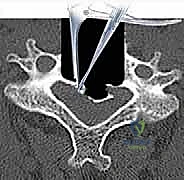

- التصوير المقطعي المحوسب (CT Scan): ضروري جداً لتقييم البنية العظمية، التكلسات (مثل OPLL)، والكسور بدقة ثلاثية الأبعاد.

الخطوة 3: استئصال الأقراص الغضروفية وجسم الفقرة (Corpectomy)

باستخدام الميكروسكوب الجراحي وأدوات دقيقة جداً، يتم أولاً إزالة الأقراص الغضروفية أعلى وأسفل الفقرة المستهدفة. بعد ذلك، يتم استئصال جسم الفقرة العظمي المتضرر بعناية فائقة لفتح مساحة واسعة وتحرير الحبل الشوكي المضغوط.